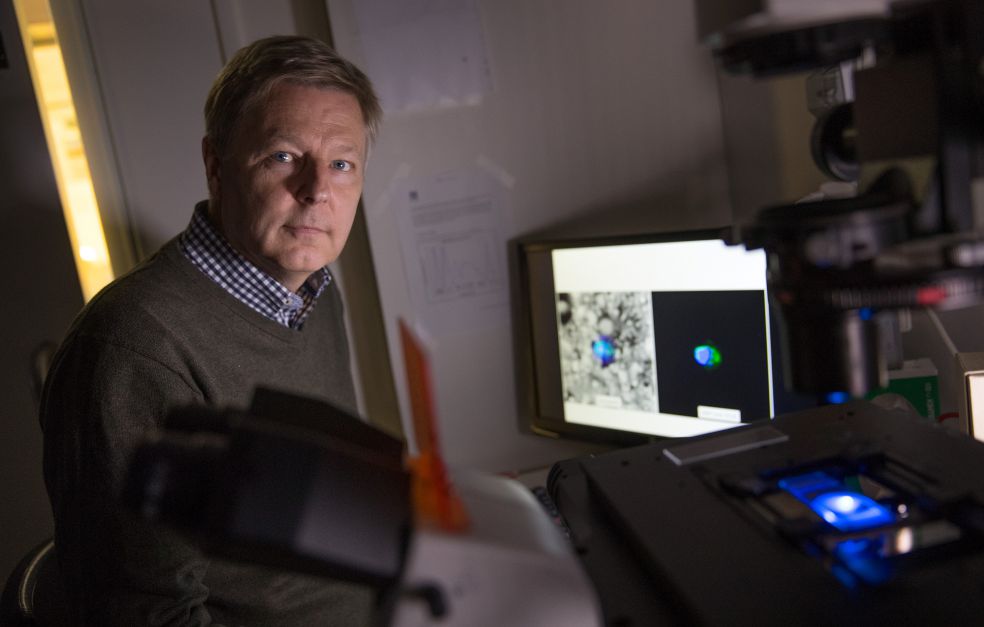

Det är tack vare optiska fibrer som vi kan surfa på internet och skicka stora datamängder i höga hastigheter härs och tvärs runt jordklotet. I de fiberoptiska kablarna används ljuspartiklar, fotoner, för att överföra information, förklarar Fredrik Laurell som är professor i laserfysik på KTH. Normalt sett håller han till i Albanova, men är nu på besök på SciLifeLab i Solna för att träffa några kollegor som uppfinner medicinska applikationer.

Optiska fibrer och lasrar kan till exempel även användas för att studera celler och bakterier in vivo, i sin naturliga miljö. Fredrik Laurell leder ett femårigt projekt om multifunktionella fibrer som har stöd från Knut och Alice Wallenbergs Stiftelse. I projektet samarbetar han med en rad forskare som har olika specialiteter inom området optisk fysik.

Fredrik Laurell arbetar sedan många år med forskare vid RISE Acreo, som tidigare hette Institutet för optisk forskning. Hans viktigaste samarbetspartner där är Walter Margulis, som även är gästprofessor på KTH, och som också ingår i projektet om multifunktionella fibrer.

I labbet på SciLifeLab demonstrerar Fredrik Laurell en mini-flödescytometer, som med flourescens och fiberoptik kan identifiera och räkna specifika partiklar i en flödande vätska. Traditionella flödescytometrar är mycket större, det här är en förenklad och miniatyriserad variant av tekniken.